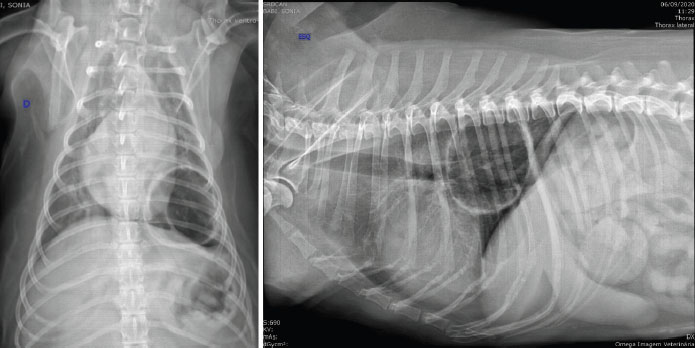

A 15-year-old mixed breed bitch, castrated, with approximately 14 kg, had sporadic coughing. Approximately 1 month before the appointment, the coughing became more frequent, she was tired easily and intolerant to physical exercise. The bitch was examined in a diagnosis center and a thoracic radiography was performed, in which we observed a large cystic emphysematous area, with thick and irregular walls, located in the left caudal pulmonary lobe (Fig. 1). The lesion measured 8.0 × 7.5 × 3.0 cm and pressed the bronchial branching of the caudal left lobe. We also observed thickening of bronchial walls, compatible with bronchopathy (Fig. 1).

Fig. 1. Thoracic radiographic images in ventrodorsal (left) and lateral (right) views, in which we observe a big cystic emphysematous area. This area has thick and irregular walls and is located in the left caudal lung lobe. It is pressing the bronchial branching of the left caudal lung lobe. We also observe thickening of the bronchial walls.